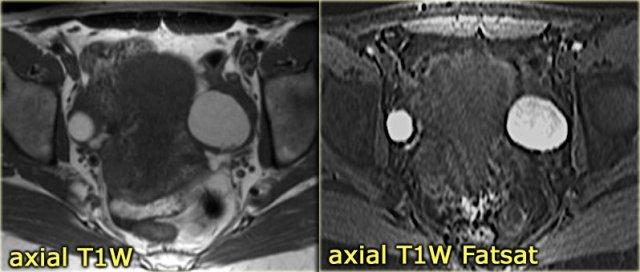

Trên hình ảnh chuỗi xung T1W mặt cắt ngang, cả hai tổn thương đều tăng tín hiệu, gợi ý mỡ, máu hoặc dịch giàu protein.

Kỹ thuật xóa mỡ không làm giảm tín hiệu trong các tổn thương này.

Trong một hình ảnh có kỹ thuật xóa mỡ tổng thể tương đối tốt, điều này loại trừ u quái chứa mỡ và xác nhận gợi ý về dịch xuất huyết.

Trên hình ảnh chuỗi xung T2W mặt cắt ngang, cả hai tổn thương đều cho thấy hình ảnh ‘shading’ điển hình.

Sự sụt giảm dần dần tín hiệu T2 được cho là do sự kết hợp của độ nhớt tăng dần và nồng độ protein cùng sắt tăng dần về phía phần thấp của tổn thương.

Không có ngấm thuốc trên hình ảnh trừ (sau tiêm Gd trừ trước tiêm Gd).

Một lần nữa, kỹ thuật trừ rất hữu ích trong các trường hợp như thế này: sự tăng tín hiệu do Gd gây ra trên nền hình ảnh trước tiêm thuốc vốn đã rất sáng sẽ rất khó nhận biết nếu không có kỹ thuật này.